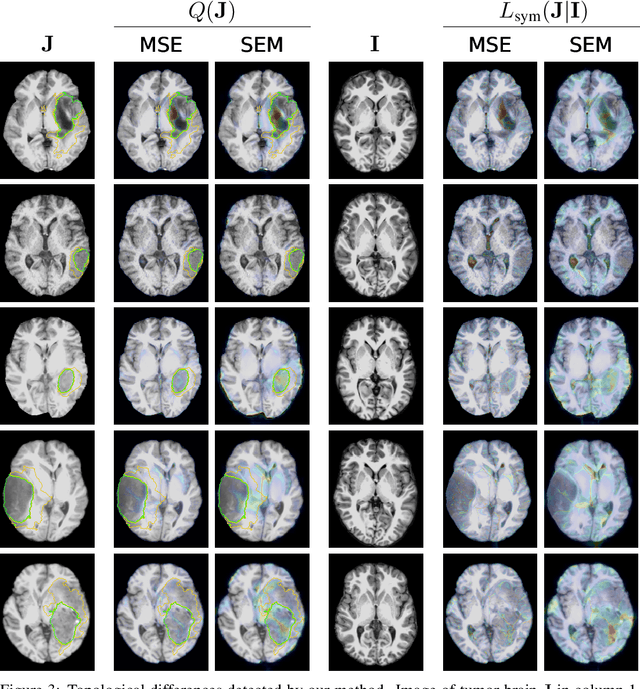

Geometric alignment appears in a variety of applications, ranging from domain adaptation, optimal transport, and normalizing flows in machine learning; optical flow and learned augmentation in computer vision and deformable registration within biomedical imaging. A recurring challenge is the alignment of domains whose topology is not the same; a problem that is routinely ignored, potentially introducing bias in downstream analysis. As a first step towards solving such alignment problems, we propose an unsupervised topological difference detection algorithm. The model is based on a conditional variational auto-encoder and detects topological anomalies with regards to a reference alongside the registration step. We consider both a) topological changes in the image under spatial variation and b) unexpected transformations. Our approach is validated on a proxy task of unsupervised anomaly detection in images.